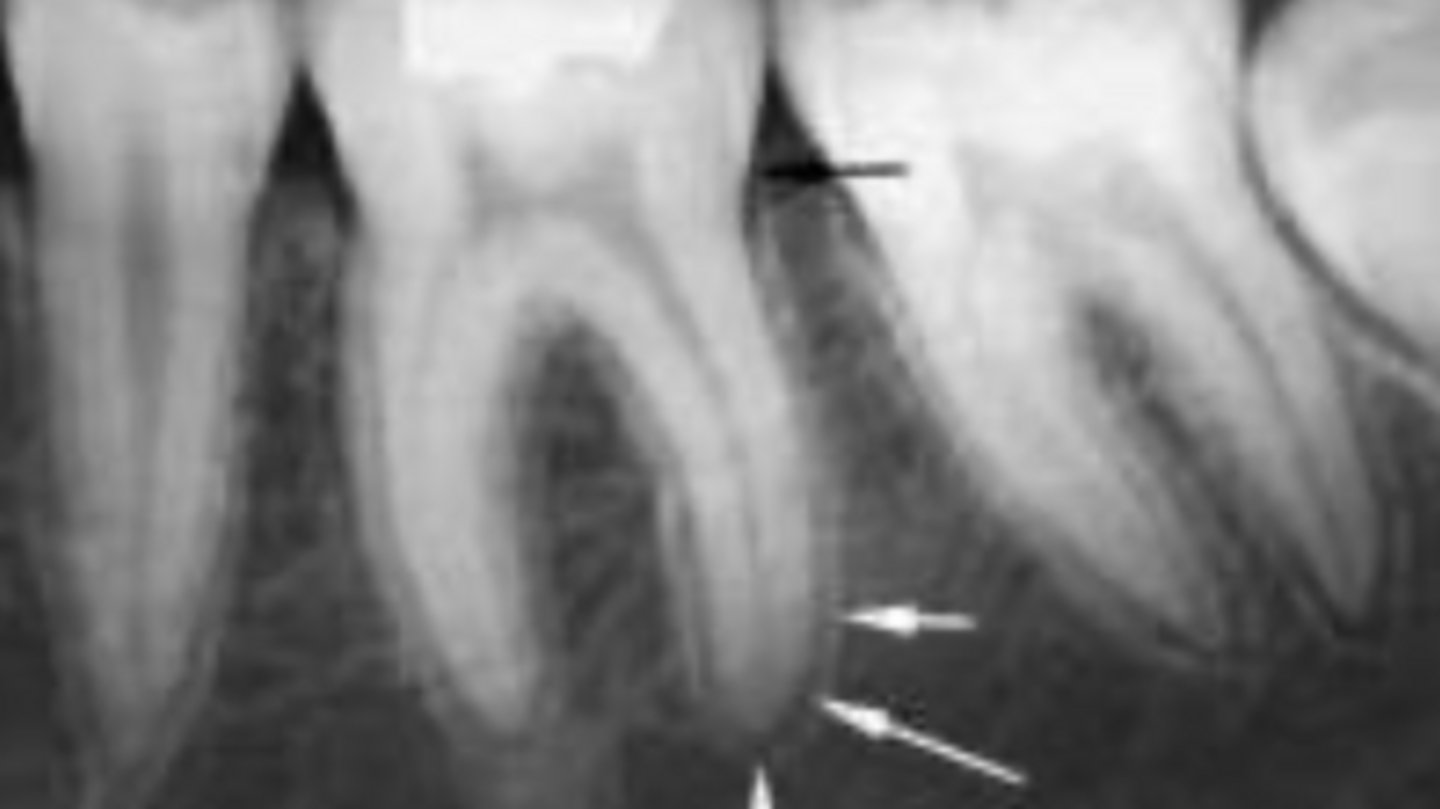

ID the problem:

- Ballooning out of root canal

internal resorption

How can you confirm if a root has internal resorption?

Take a few different angles